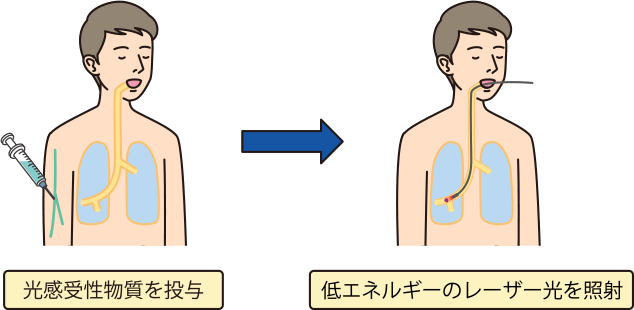

気管支鏡を使った検査は、肺がんだけでなく、肺のさまざまな病気の検査としておこなわれています。気管支の粘膜や気管支がふさがっていないかどうかの観察、病巣の一部を採取、気管支内の異物除去、レーザー照射の治療にも用いられています。